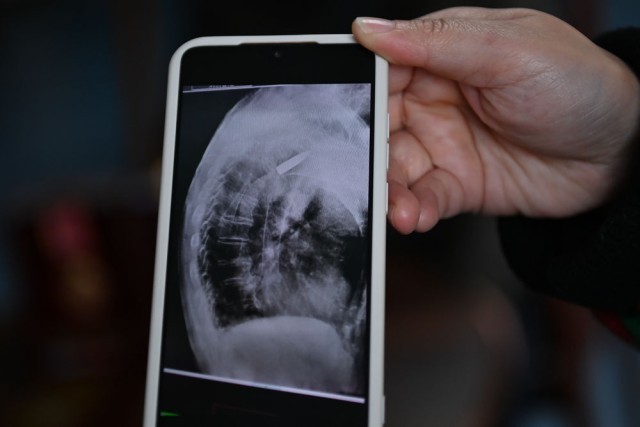

2022年,平湖市第一人民医院在给老人做食道支架置入手术时,X射线下清晰地看到老人肩膀里有颗长约3.5厘米的子弹。而这颗子弹,早已与老人的骨头粘在了一起,无法取出。

医院的放射线视觉指引图像显示,罗锦文老人右侧肩膀里有一颗长约3.5厘米的子弹(3月2日摄)。新华社记者 黄宗治 摄